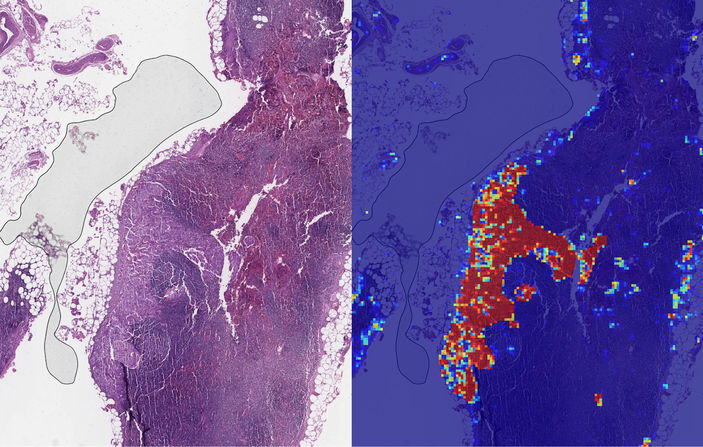

Google AI ekibinin ABD’de San Diego Donanma Sağlık Merkezi ile birlikte yaptığı çalışmada araştırmacılar, lenf nodu biyopsilerini otonom olarak değerlendiren kanser tespit algoritmalarını kullanarak, önemli bir başarı oranı yakaladı. Araştırmada kullanılan Google’ın derin öğrenme aracı, iki patoloji slaytı setini kullanarak tümörlerin karakteristik özelliklerinin tespitini mümkün hâle getirdi.

Bu sistemin kanserin yayılmasını çok farklı koşullarda görebildiği ifade edilen araştırma sonucuyla ilgili yapılan açıklamada, Google’ın derin öğrenme (deep learning) modelini temel alan yapay zeka algoritmasının kanserli ve kansersiz slaytlar arasındaki farkı yüzde 99.3 oranında doğru tespit edebildiğine dikkat çekildi. Açıklamada, ayrıca geliştirilen bu sistemin insan gözünden kaçabilecek küçük yayılımları bile fark edebildiğinin altı çizildi.

Patalogların işlediği meme kanseri hastalarının lenf bezlerinden alınan doku örnekleriyle birlikte analiz işlemini yapan yapay zeka modülü, kanser hücresinin ne kadar agresif bir ilerleme kaydettiği ve vücuda ne kadar yayılmış olabileceğini de ortaya koyuyor.

Geliştirilen yöntemin patoloji uzmanları tarafından destekleyici bir araç olarak kullanılabileceğini belirtilirken, LYNA (LYmph Node Assistant) adı verilen bu aracın gelişim sürecinin tamamlanmasıyla kanserin yayılma sürecindeki küçük sıçramaların inceleme süresini de yarı yarıya indirilebileceği aktarıldı.